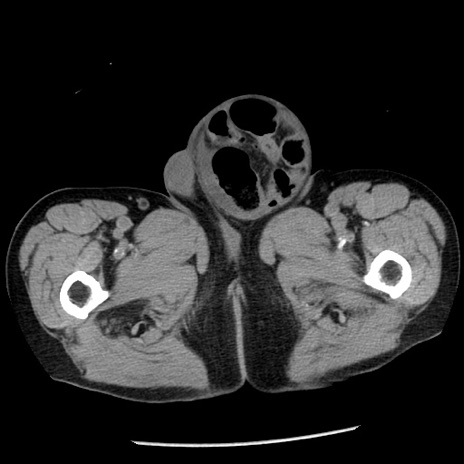

症例26(横断像)

【症例】80歳代男性

【主訴】嘔吐

【現病歴】昨晩2回嘔吐あり、今朝になっても嘔吐あり。来院。

【既往歴】胃潰瘍

【身体所見】意識清明、BT 37.6℃、BP 166/95mmHg、HR 100bpm、SpO2 97%、腹部:平坦・軟、腸蠕動音聴取良好、圧痛なし。

【データ】WBC 21900、CRP 1.46